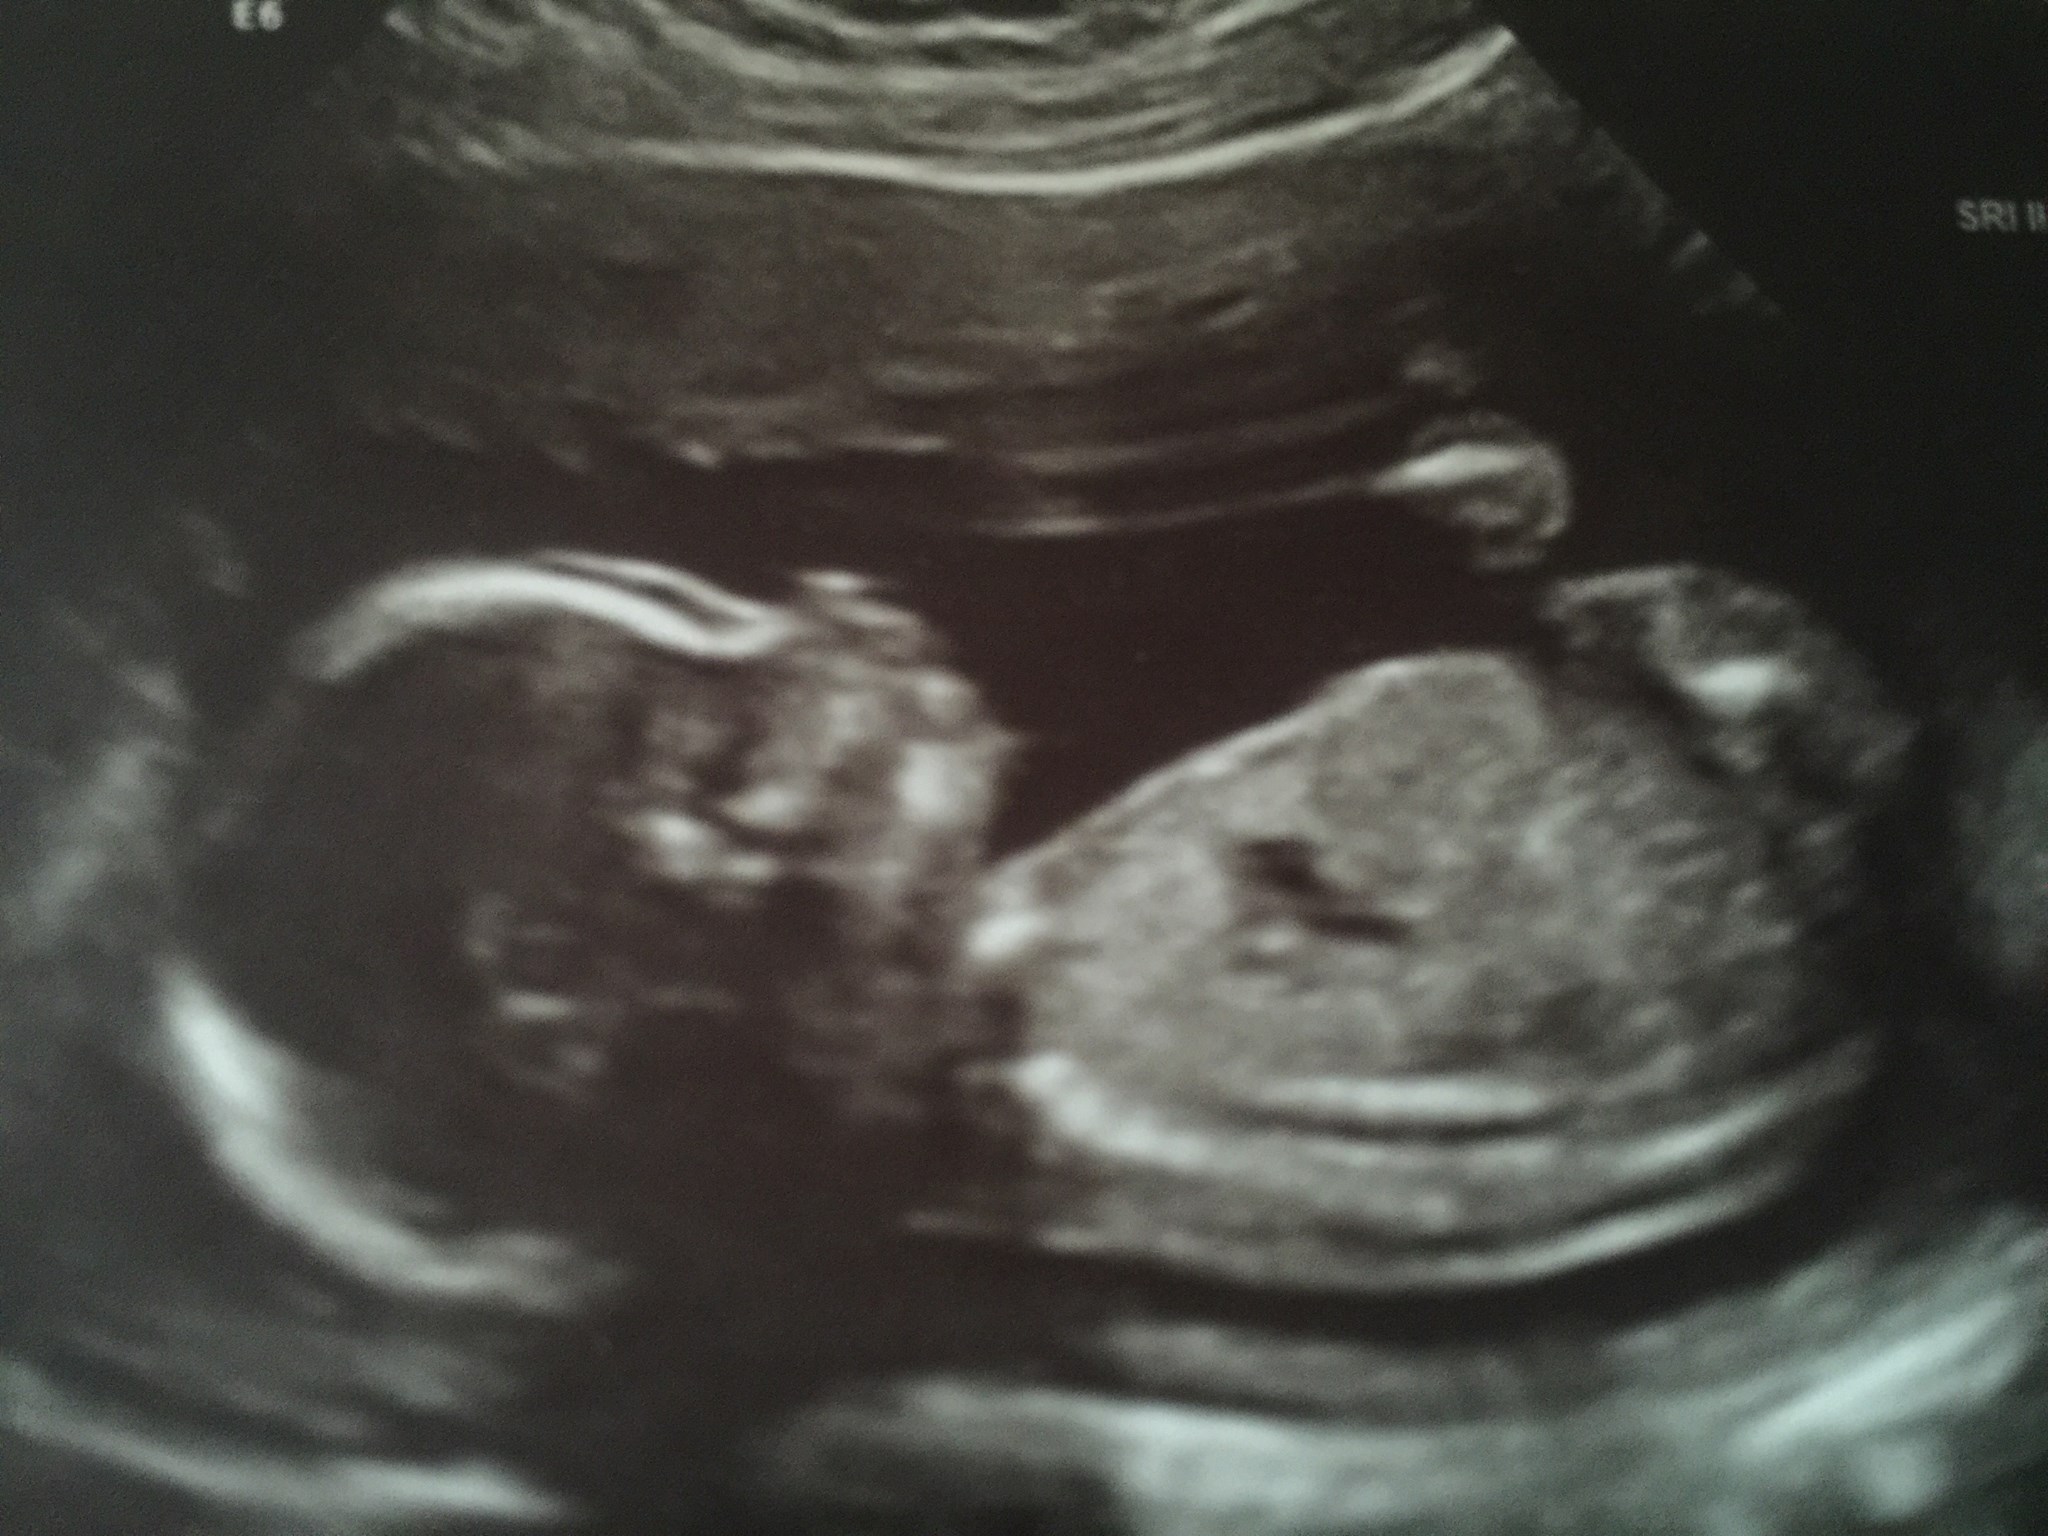

Max had some big hurdles to overcome even in the early stages:

19 weeks: anatomy scan shows his corpus callosum (connects the two hemispheres of the brain) might be missing

25 weeks: pediatric neurologist reads his fetal MRI and mentions a rare genetic syndrome could be present

32 weeks: Max is born prematurely with hydrocephalus (excess fluid in the brain)

And yet, he was born looking like this, ready to take on the next challenge with a smile on his face.